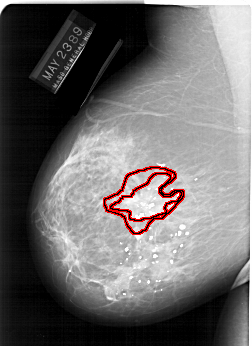

FILE: A_1247_1.LEFT_MLO.OVERLAY

TOTAL_ABNORMALITIES 1

ABNORMALITY 1

LESION_TYPE MASS SHAPE IRREGULAR MARGINS SPICULATED

ASSESSMENT 5

SUBTLETY 5

PATHOLOGY MALIGNANT

TOTAL_OUTLINES 2

BOUNDARY

CORE